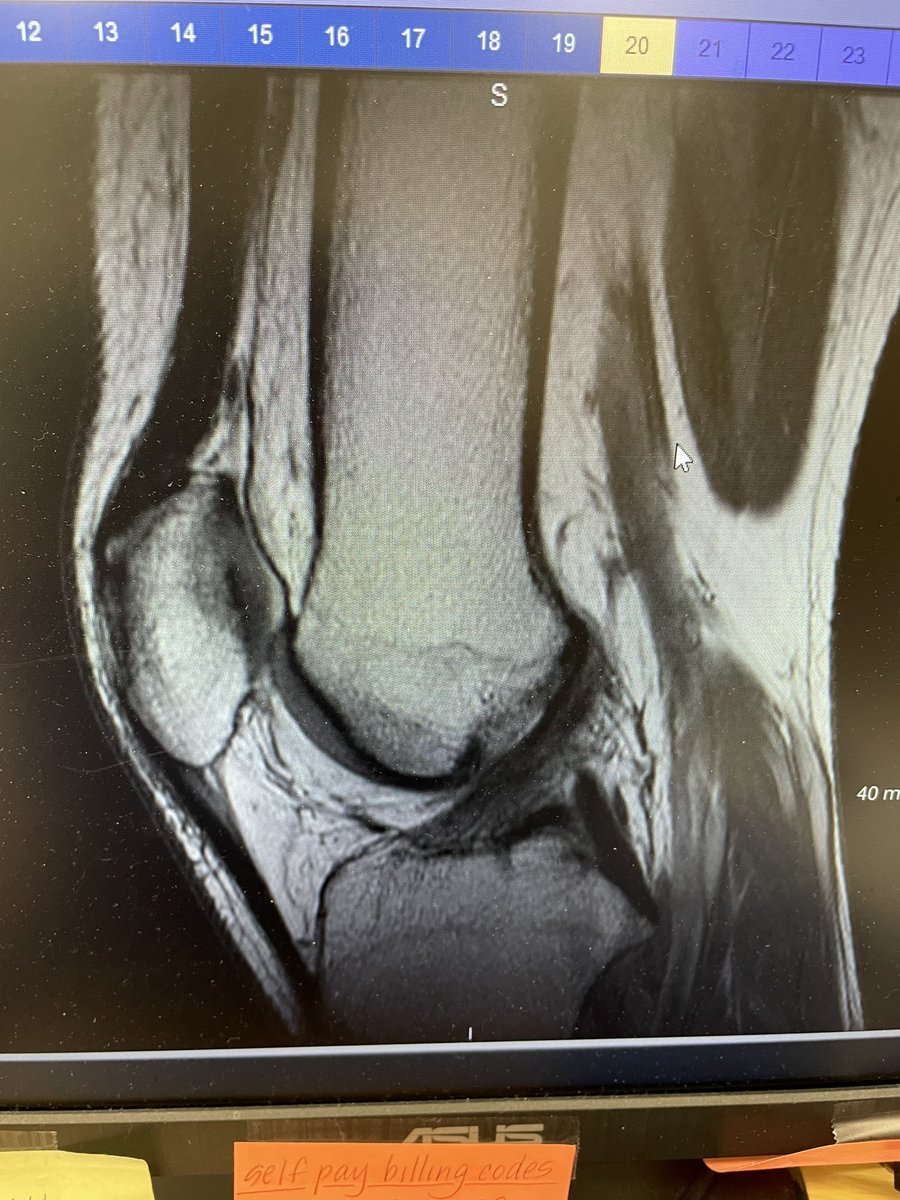

أخصائي علاج طبيعي لإصابات العظام و المفاصل و العضلات | عيادتي @Jointclinic_sa

من الاختبارات للمنتخب السعودي للبادل Joint clinic | عيادات جوينت بادل السعودية | Saudi Padel